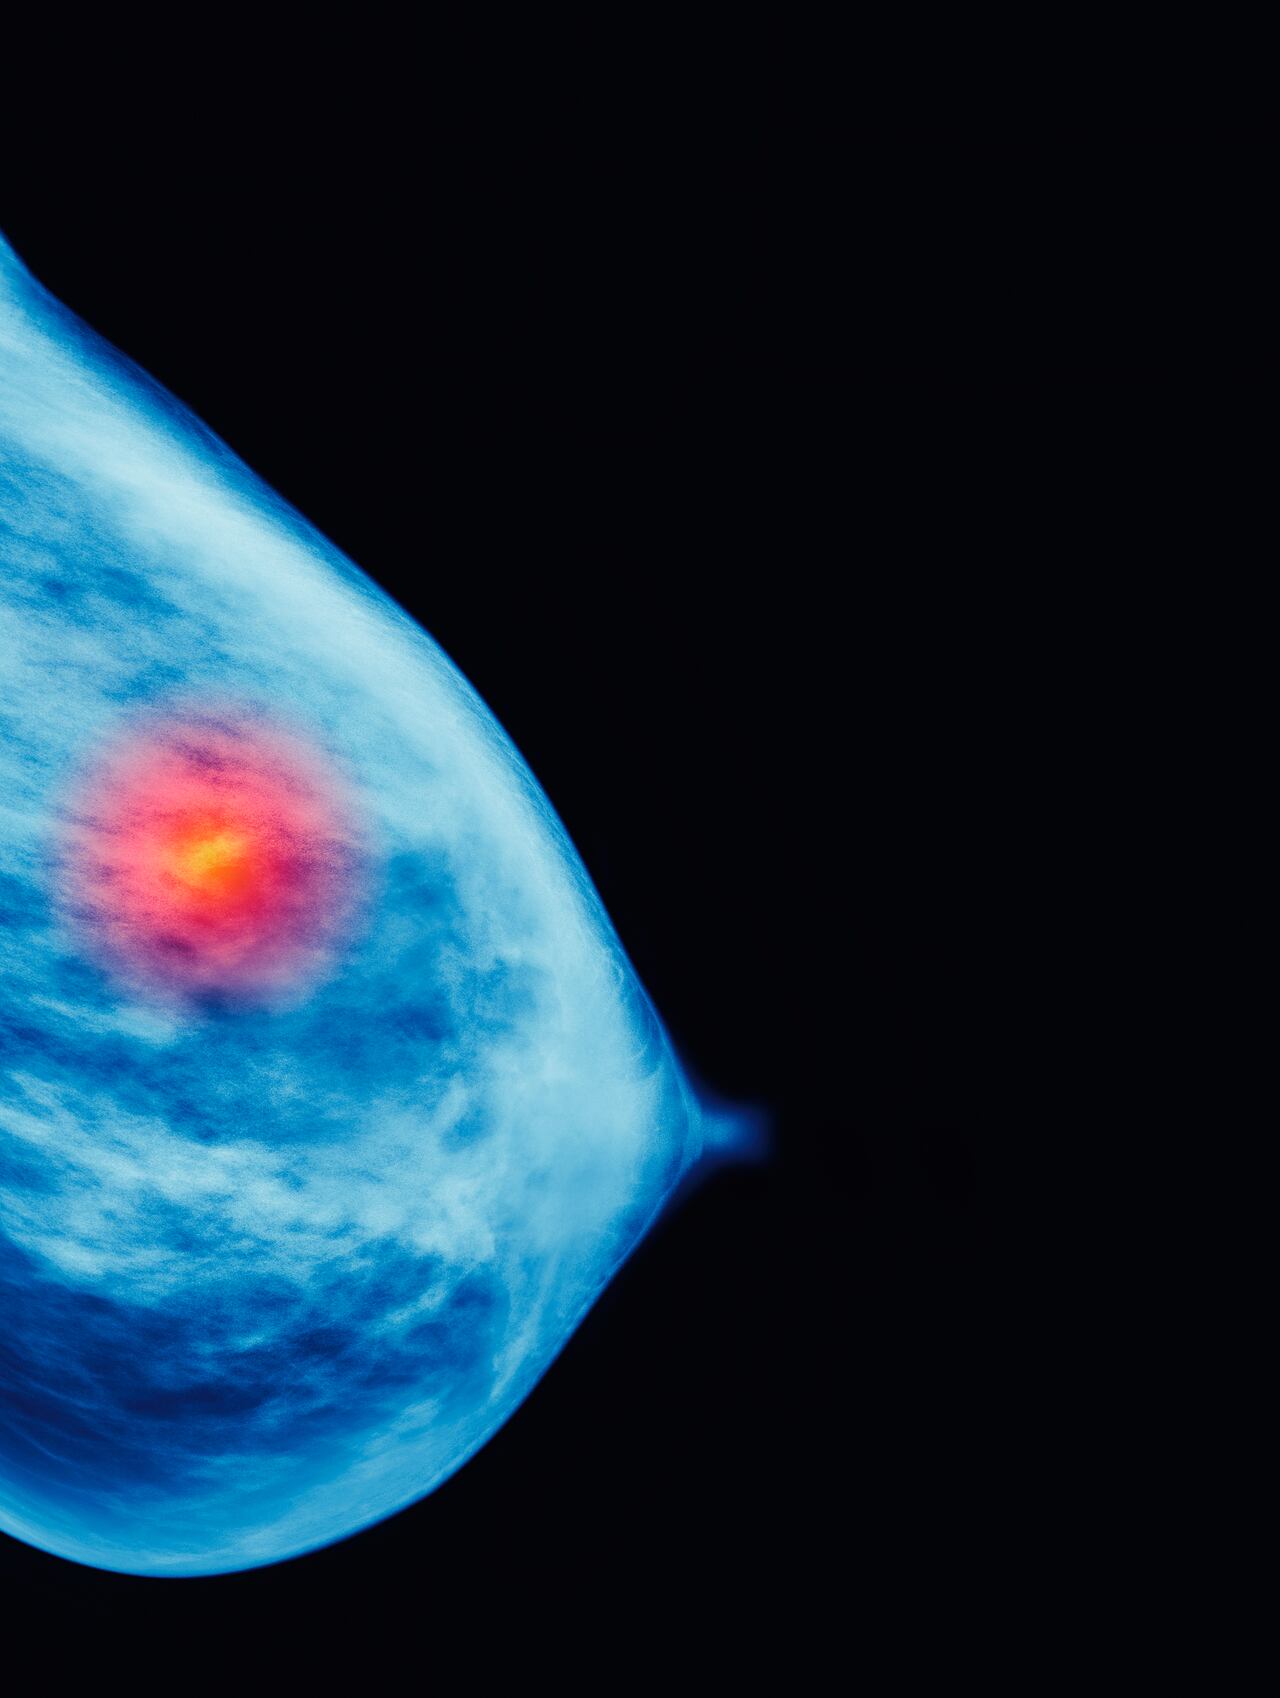

Cáncer de mama: cerca del 10% es hereditario; la detección temprana es la clave

La detección reduce el riesgo de padecer la enfermedad.

El 5 % de todos los cánceres es hereditario y, en concreto, en los cánceres de mama y ovario, esta cifra puede llegar hasta el 10 %, debido a que la paciente es portadora de una mutación o variante genética. Sin embargo, esta podría identificarse con un test genético para identificar el riesgo de padecer la enfermedad e implementar medidas preventivas y terapéuticas.